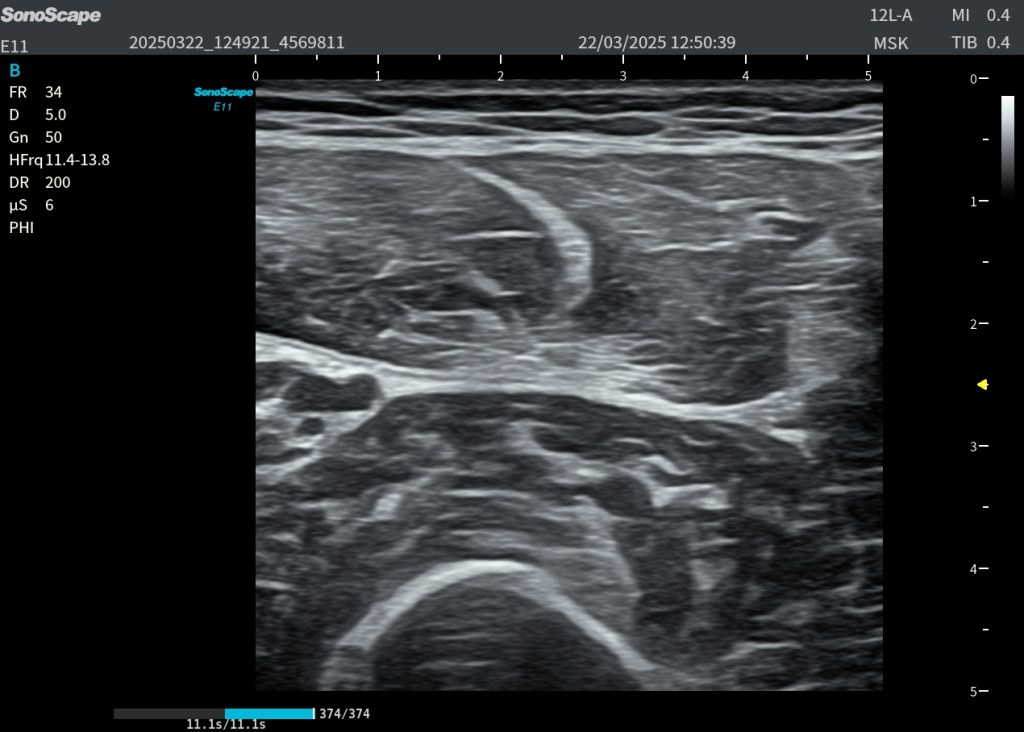

La exploración ecográfica de la planta del pie, es compleja, multitud de estructuras en muy poco espacio, pero debe tener y tiene. en mi opinión un punto de partida muy claro: el reconocimiento del plano muscular superficial y la progresión ordenada hacia los planos profundos. Las imágenes mostradas representan exactamente ese recorrido, combinando un corte transversal con su correlación en longitudinal, lo que permite entender una ecoestructura básica y músculo vascular, como punto de partida de la exploración de la planta del pie.

En el corte transversal, la primera estructura que aparece de forma constante es el flexor corto de los dedos (1). Se presenta como una masa muscular hipoecoica con un patrón fibrilar interno, reconocible por su tamaño, que ocupa prácticamente todo el plano superficial. Este músculo no solo es fácil de identificar, sino que actúa como una auténtica “puerta de entrada” a la anatomía plantar: si no lo reconoces con claridad, es muy probable que estés fuera de plano.

Justo por debajo de este músculo aparece una estructura mucho más brillante, lineal, que contrasta claramente con el tejido muscular: la aponeurosis del flexor largo de los dedos (2). Ecográficamente, su aspecto hiperecogénico y continuo la delata como una estructura tendinosa/aponeurótica. Esta línea no solo separa planos, sino que marca el paso hacia una anatomía más compleja y profunda.

Al atravesar esta referencia, entramos en el territorio del cuadrado plantar (3). A diferencia del plano superficial, aquí el patrón muscular es más compacto, homogéneo y menos organizado visualmente, lo que puede generar dudas si no se conoce bien la anatomía. Este músculo, profundo y funcionalmente ligado al flexor largo de los dedos, es clave porque nos sitúa justo encima del plano vascular.

En este mismo nivel profundo, y con una disposición característica, aparece el tendón del peroneo largo (4). Su identificación es especialmente importante: se observa como una estructura claramente fibrilar, hiperecogénica y bien delimitada, con un trayecto oblicuo que rompe la simetría del resto de estructuras. Este tendón es una referencia anatómica de enorme valor, porque confirma que estamos en el plano correcto y orientados adecuadamente dentro del mediopié.

Finalmente, en el nivel más profundo de la imagen, aparece la estructura que da sentido a toda esta organización: el arco plantar profundo (5). En modo B puede pasar desapercibido o verse de forma incompleta, pero con Doppler se revela como una estructura vascular bien definida. No es un vaso aislado, sino una anastomosis arterial que representa el eje vascular plantar profundo.

Cuando pasamos a la imagen en plano longitudinal, toda esta anatomía se reorganiza y cobra aún más sentido. El flexor corto de los dedos (1) se transforma en una estructura alargada, donde su patrón fibrilar se hace más evidente y continuo. El cuadrado plantar (3) se observa como un plano muscular profundo más compacto, mientras que el tendón del peroneo largo (4) destaca claramente por su morfología lineal y su continuidad, facilitando su seguimiento dinámico. La aponeurosis, aunque más sutil, sigue actuando como una línea de separación entre planos.

Pero hay un elemento especialmente relevante desde el punto de vista anatómico y ecográfico: el llamado triángulo arterial plantar. Este concepto, que se aprecia especialmente en la imagen con Doppler, está formado por la arteria plantar medial, la arteria plantar lateral y el propio arco plantar profundo. Más que una figura geométrica estricta, es una forma de entender la disposición vascular en este plano. Identificar este triángulo significa que estás exactamente donde debes estar.

Fíjate en los pictogramas, en las referencias musculares y vasculares, usa el Doppler, te recomiendo el Power, por su mayor sensibilidad y parte desde un punto de partida con la anatomía estudiada. Desde el punto de vista práctico, este conjunto de referencias permite algo fundamental: Orientarse. La ecografía plantar no consiste en reconocer estructuras aisladas, sino en entender cómo se relacionan entre sí en profundidad. El músculo superficial te introduce, la aponeurosis te guía, el cuadrado plantar te posiciona, el tendón peroneo largo te confirma y el arco plantar profundo te valida y desde ahí seguiremos estudiando el pie, en próximos Post.